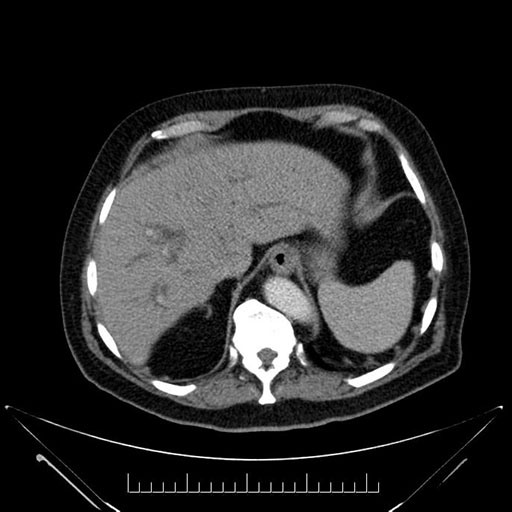

Axial - stented